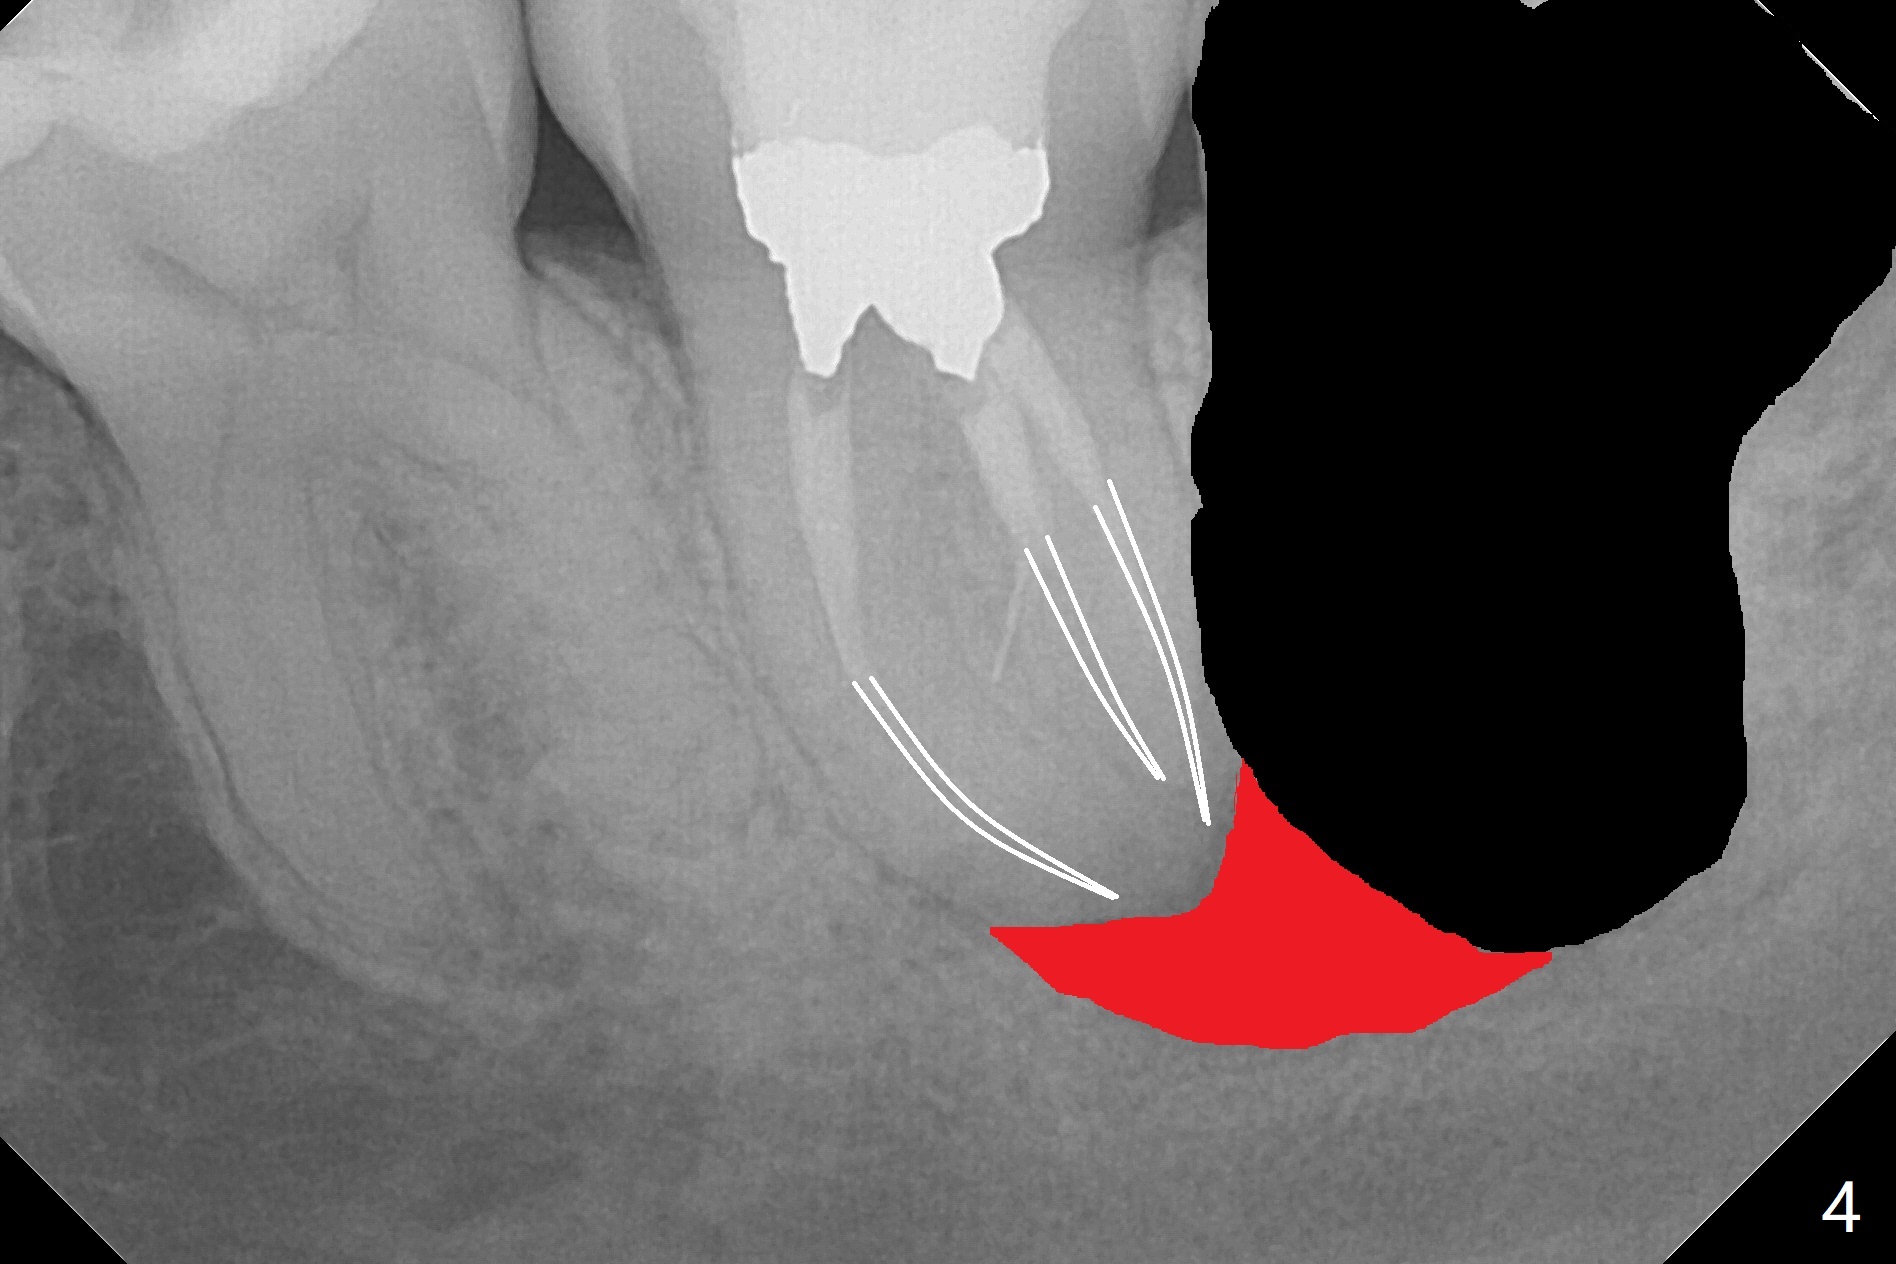

A 37-year-old woman requests extraction of the 3rd molars and orthodontic retreatment (Fig.1). Since the bone between #17 and 18 is thin and short (Fig.2 black *), bone graft is needed after #17 extraction. But the apical infection at #18 (Fig.2 white *) may affect graft survival. The patient agrees to have RCT retreatment done (Fig.3 white curved lines) before extraction (black area). The apical granulation tissue can be removed (Fig.4 red area) prior to bone graft (Augma). The latter will be also placed at #17 as a control. After endodontic consultation, the patient does not want RCT retreatment. She would like to have the 3rd molars extracted first and #18 removed if needed. After #17 extraction (Fig.5), apicoectomy will be performed at #18 (Fig.6 (white outline: surgical bur, use non-torque handpiece)). Following curettage of the apical lesion at #18 (Fig.7), bone graft will be placed (Fig.8 red circles). In fact the patient insists upon #1, 16, 17, and 32 extraction. After extraction, allograft (Fig.9 A (Ossogen, Mineralized Cort/Can (30%/70%), .25-1.0 mm) is placed in the mesioapical of the sockets of #17 and 32, while Osteogen Plug (O) and BioXclude in the distocoronal one (4-0 PGA suture). There is minimal bone between the 2nd and 3rd molars (black arrowheads). The allograft is intentionally pushed into #18 apical defect after enucleation (white arrowhead). The sockets are slightly open, although sutures are in place 2 weeks postop (Fig.10,11). It is unknown whether the bone graft is partially dislodged or not.